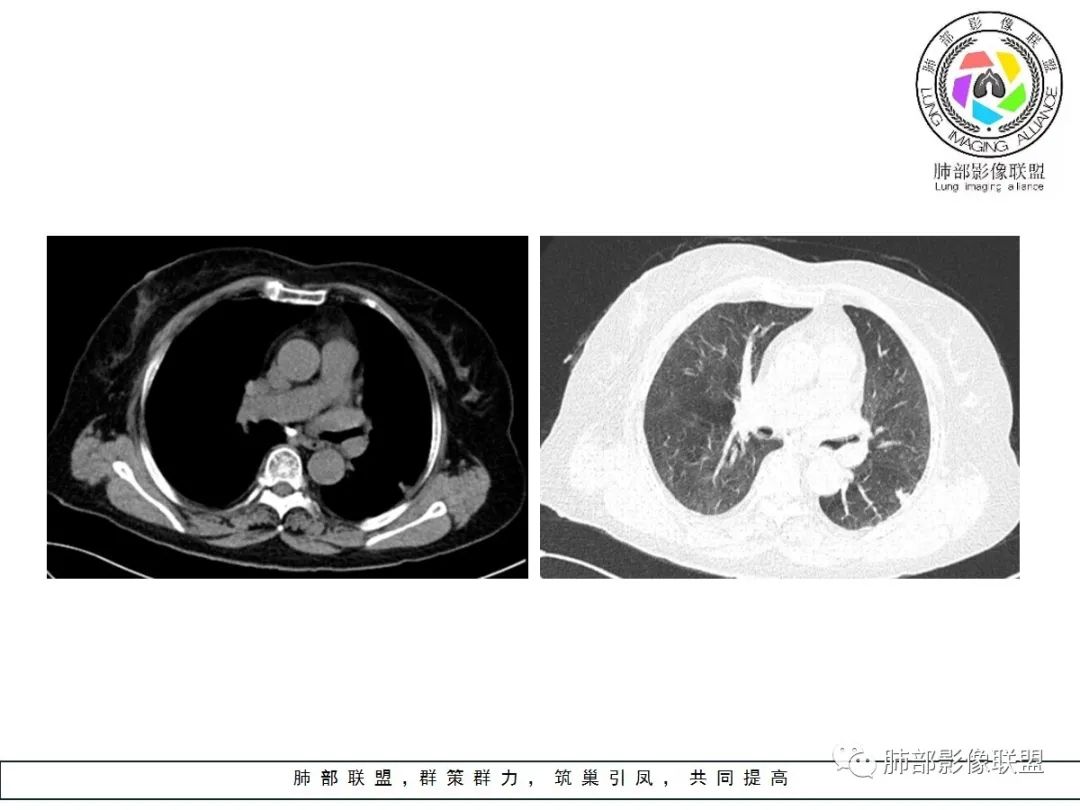

左肺下叶的不规则病灶,有恶性征象,有深分叶,病灶有支气管进入截断了,病灶里支气管扩张;良性征象有平直征,病灶强化明显,脂肪间隙存在,肉芽肿病变鉴别肌纤维母细胞瘤 医学百科网 | YxBaike.Com

老年女性,左肺下叶的不规则病灶,深分叶,病灶有支气管进入截断,血管集束,斜裂牵拉,但胸膜干净,有平直征,病灶强化明显,最后还是考虑恶性,鉴别隐球 医学百科网 | YxBaike.Com

左肺下叶背段胸膜下不规则结节,有良性征象:有平直、U形凹陷,胸膜下脂肪间隙清晰,明显强化;又有些恶性征象:有分叶,叶间胸膜牵拉。 医学百科网 | YxBaike.Com

有些纠结,还是考虑恶性(腺癌可能)> 炎性肉芽肿 医学百科网 | YxBaike.Com

临床无特殊。良性征像:冠状位方正,直边征,横断位略呈三角形,尖端指向肺门。恶性征像:小结节堆积样改变,轻度强化,增加20hu左右。横断位多分叶、毛刺。斜裂牵拉内收,胸膜被掀起伴局部少量积液,病灶底部似凸于胸膜外。腺癌与炎性肉芽肿病变的鉴别。强化方式及周边情况,结核可能小。收缩力很大,把腺癌放第一吧。

老年,实验室无异常,左肺结节,同胸膜宽基底相连,密度均,胸膜下脂肪存在,增强明显不均匀强化,考虑良性病变,炎性肉芽肿,结核,隐球。

良性征象(宽基底与胸膜相连,没有明显胸膜凹陷与微积液,收缩力较弱,仅仅叶间胸膜略凹陷,边缘平直,U形凹陷为主,结节较散,增强动脉期强化太明显)>恶性征象(局部略有膨隆,叶间胸膜略凹陷),可疑征象(图像不太好,支气管截断不确定,分叶征象不确定,也可能是散在结节的假象,脐凹征可疑),综合考虑良性结节可能大(隐球?结核?其他炎性结节?局部肺栓塞?)腺癌待排,临床简单,穿刺一下就OK。 医学百科网 | YxBaike.Com

左肺下叶胸膜下结节,边缘部分平直收缩部分膨隆,可疑脐凹征,邻近叶间裂稍牵拉,胸膜糊墙,增强扫描均匀强化,老年女性,良恶性征象都有,平扫密度似略偏高,先考虑良性,隐球菌?一般炎性肉芽肿?腺癌待排,老年人,警惕性提高一个级别,治疗后复查或穿刺活检。 医学百科网 | YxBaike.Com

左肺下叶前基底段斑片状影,边界清楚,增强强化15Hu,冠状位矢状位,边缘平直,胸膜下胸膜外脂肪间隙尚清楚,轻度强化,先抗炎,三个月复查。

有胸膜牵拉,老年女性,角蛋白19片段稍高,部分层面稍膨隆,呈球形,边界太清楚,恶性待排除,先抗炎,三个月复查。

老年女性,左肺下叶背段一节结影,近靠胸膜下,边缘分叶状,中等强化,强化均匀,周围肺叶见小结节影,考虑结核肉芽肿,不排除恶性结节,腺癌可能。 医学百科网 | YxBaike.Com

边缘平直

宽基底与胸膜相连

这条血管让我不踏实,像脐凹征吗? 医学百科网 | YxBaike.Com

其他的都是炎性特点,恶性待排吧

就是这个脐凹征有恶性的特点,所以恶性肯定不能排除 医学百科网 | YxBaike.Com

一、本例恶性征象较有特征的是脐凹征。 医学百科网 | YxBaike.Com

1.脐凹征:分叶状结节局部凹陷的部位受到血管阻力而形成,表现为血管进入分叶之间,脐凹相对比较对称光滑,近肺门侧多见,与血管走行方向一致。 医学百科网 | YxBaike.Com

2.95%见于恶性肿瘤,5%为炎性病变。 医学百科网 | YxBaike.Com

3.病灶显著强化不支持结核;边界清楚,肺门一侧波浪状改变,患者为老年女性,缺乏临床表现,尽管影像有一些炎性灶特点,但恶性肿瘤性病变不能除外。 医学百科网 | YxBaike.Com